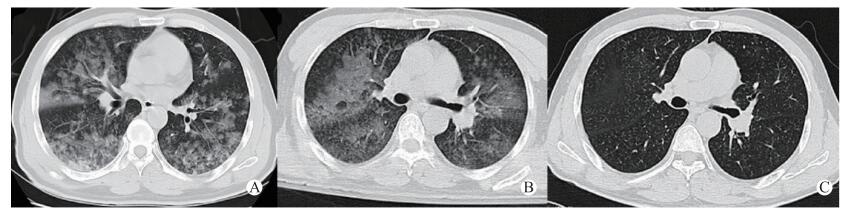

| 图 1 患者入院2 h(A)、第3天(B)及第5天(C)胸部CT变化 |

1 资料与方法患者,男,45岁。因“吸入氯气后胸闷气急伴视物模糊9 h”于2017年5月7日晚8时入我院急诊。患者9 h前家务劳动时不慎吸入氯气,当时稍有胸闷气急,伴视物模糊,流泪不止,用大量清水冲洗眼部,未做特殊处理; 后患者胸闷气急症状逐渐加重,伴有咳嗽,无胸痛,来我院急诊就诊。查体:T 37℃,BP 145/89 mmHg(1 mmHg=0.133 kPa),HR 121次/min,RR 28次/min,急诊室测患者未吸氧情况下氧饱和度为70%,神志清,两肺可及少许湿啰音,腹软,无压痛、反跳痛、肌紧张。立即予储氧面罩吸氧后氧饱和度维持在90%~95%左右,急诊血气分析提示, pH 7.37,PO2 68.4 mmHg, PCO2 44.3 mmHg, BE -2.57 mmol/L, SB 22.3 mmol/L。查胸部CT(图 1A)提示,两肺广泛斑片状影; 其余血检查基本正常。初步诊断:1.氯气中毒; 2.急性呼吸窘迫综合征,为进一步治疗收住急诊ICU病房。

入我科急诊ICU后予继续给予储氧面罩吸氧,氧饱和度仅能维持在90%~92%,RR:35次/min,HR:135次/min; 患者自诉胸闷气急症状不能缓解,呈端坐位呼吸。与家属充分沟通后改为经鼻高流量吸氧治疗:初始吸入氧体积分数70%, 氧流量50 L/min; 同时给予甲强龙80 mg静滴,沐舒坦化痰及雾化吸入等对症治疗,患者氧饱和度逐渐上升至98%~100%,并自诉胸闷气急症状明显缓解,可平卧。使用高流量氧疗1 h后复查血气分析:pH 7.38,PO2 88.4 mmHg,PCO2 23 mmHg, BE-1.36 mmol/L, SB 23.3 mmol/L; 后患者病情逐渐稳定,氧饱和度维持在95%~99%,仍稍有胸闷气急症状,有咳嗽咳痰,痰容易咳出。3 d后复查胸部CT提示(图 1B):两肺斑片影较前吸收,经鼻高流量吸氧治疗模式调整为:吸入氧体积分数40%, 氧流量30 L/min。患者氧饱和度基本维持在96%以上,胸闷气急症状基本消失,仍稍有咳嗽,无咳痰,入监护室5 d后患者病情好转后转入普通病房,改为普通鼻导管吸氧治疗,7 d后再次复查胸部CT提示(图 1C),肺部斑片状影基本吸收,患者无明显不适主诉,予出院并嘱其定期复查胸部CT。